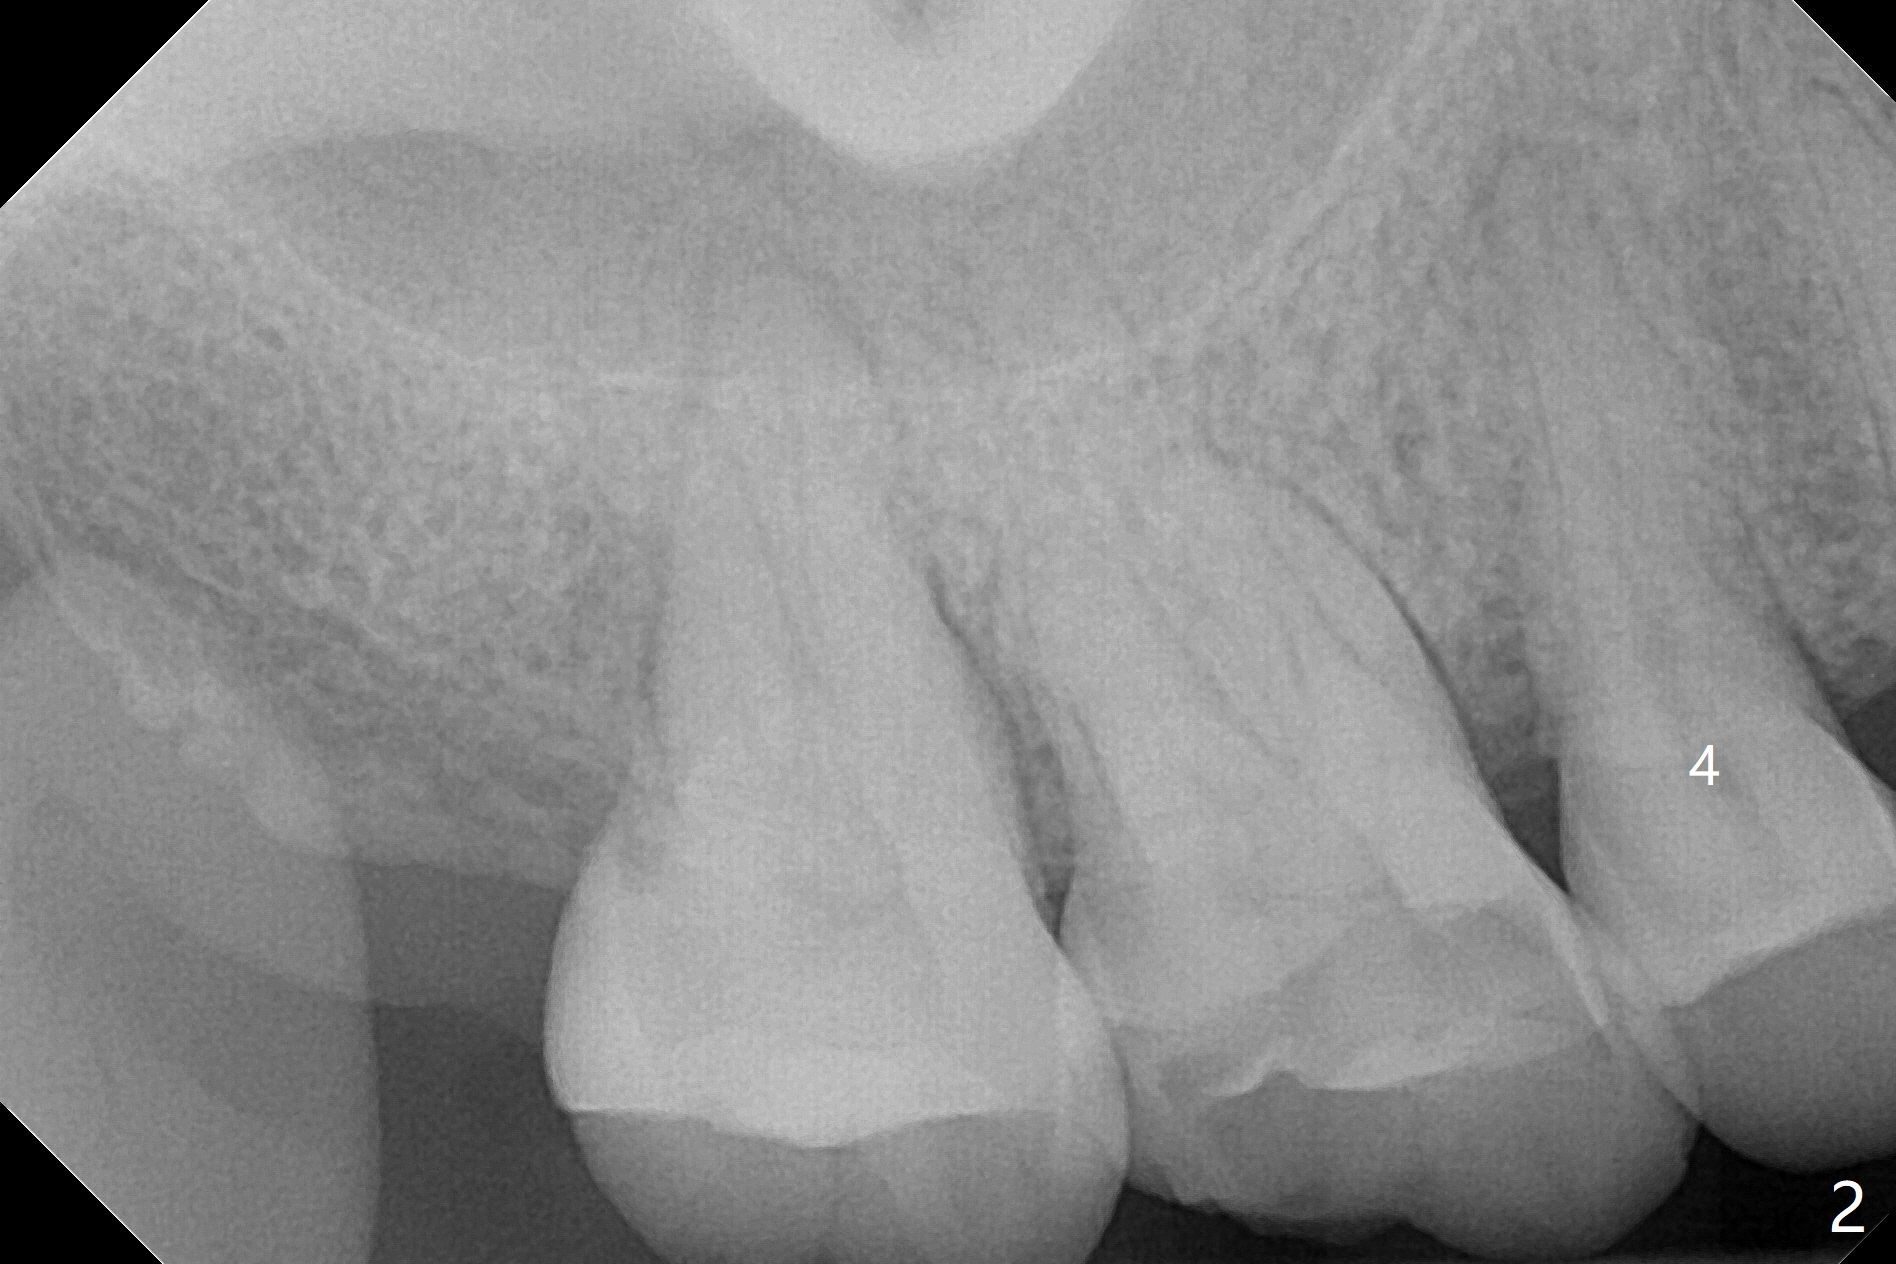

Buccal Apical Defect

A 52-year-old woman had palatal periodontal infection at #2 a half month earlier (Fig.1,2), which was treated with Arestin. When she returns, the tooth #4 has palatal subgingival oblique fracture (Fig.3 <), interfering with mastication. Due to emergency, free hand immediate implant is planned. The buccal apical defect (Fig.3 *) will be repaired with PRF membrane (x1) and allograft after osteotomy (with gauze in place). A 4.5x20 mm tissue-level implant will be placed (Fig.4) instead of a bone-level one (Fig.5).